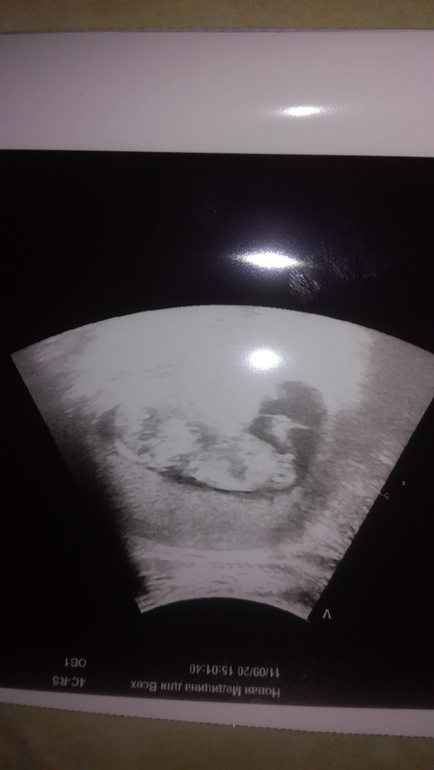

На УЗИ предположили мальчика😍. Мальчишка же да? Ведь да?

У вас он тоже явно не параллельно позвоночнику, пиптик вверх 💪🏼

А по мне бугорок совсем не лежит!!! Он же явно смотрит вверх, у девочек по другому!

Пацаааан это 😉 голубой чиииих на вас 🤧💦